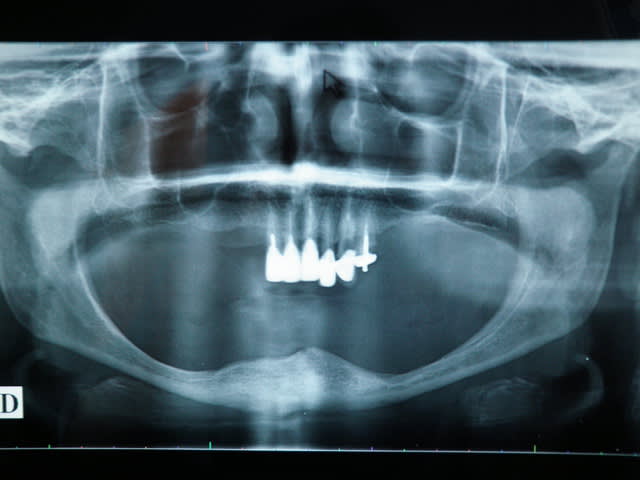

celle-la non plus....67ans

MANDIBULE Là tu poses 4 à 5 implants en flapless de 5 à 5 pour ne pas dépérioster la zone symphysaire et deux plaques en apposition pure en distal en full flap bien sûr

MAXILLAIRE Pas un cas difficile en basale...